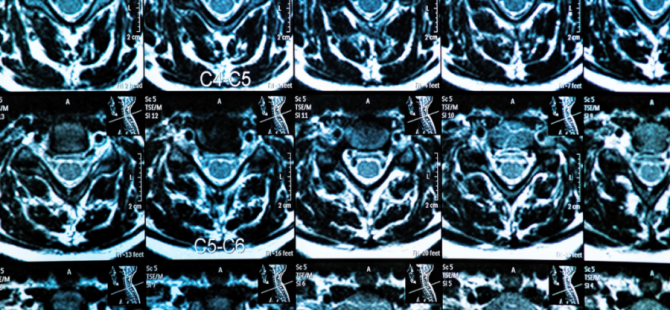

அவர்களிடம் இருக்கும் தரம் கெட்ட எம்.ஆ.ஐ (MRI) ஸ்கான் சம்மந்தமான செய்தி சில வருடங்களுக்கு முன் ஊடகங்களில் வெளிவந்தது.

கீழே படத்தில் இருப்பது மருத்துவர் ஒருவரின் முகநூலில் பெறப்பட மேற்படி தனியார் வைத்தியசாலையில் பெறபட்ட தரமற்ற எம்.ர்.ஐ (MRI) ஸ்கேன் படம்.

இனி கொழும்பில் உள்ள வைத்தியசாலையில் எடுக்கப்பட்ட அதே மாதிரியான ஸ்கேனின் படத்தினை கீழே பார்க்கலாம்.

சாதரண மக்களுக்கே இது எவ்வளவு தரமற்ற, தெளிவில்லாது என்று இலகுவாக புரியும். எனவே மக்கள் இது தொடர்பாக அவதானமாக இருக்க வேண்டப்படுகின்றனர்.